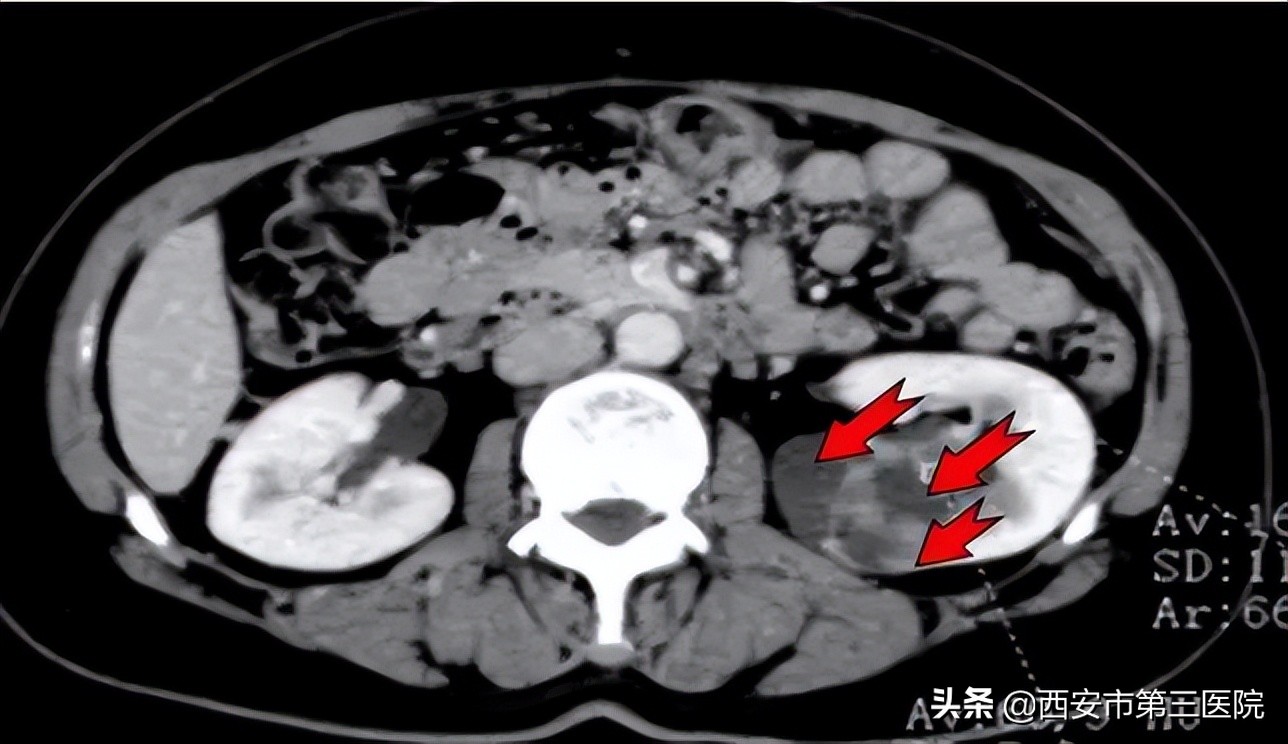

•II级(良性):囊内容物少许混杂,边缘锐利,囊肿可有分隔(<1mm),可有小钙化。均质的高密度囊肿(<3cm;CT值>20HU),囊肿边缘清楚,增强CT囊肿密度无改变。处理:通常认为是良性的,不用处理。但是如果囊肿的体积较大≥ 3 cm,CT值>20HU或者出现较厚的结节样钙化,可能囊肿会被归为IIF级囊肿,IIF 级囊肿有相对较高的恶性倾向,建议严密随访每半年随访CT 或MRI增强,出现变化建议手术。

我们可以从上面CT影像图看出,在囊肿的内部出现了分隔(箭头标记的位置为分隔),这个分隔将整个囊肿分为上下两个部分,但是分隔比较小且规则。

II型囊肿一般来讲大部分为良性,恶性比例可能仅有5%-10%,这类肿瘤我们暂时不用手术切除,但是需要定期复查。